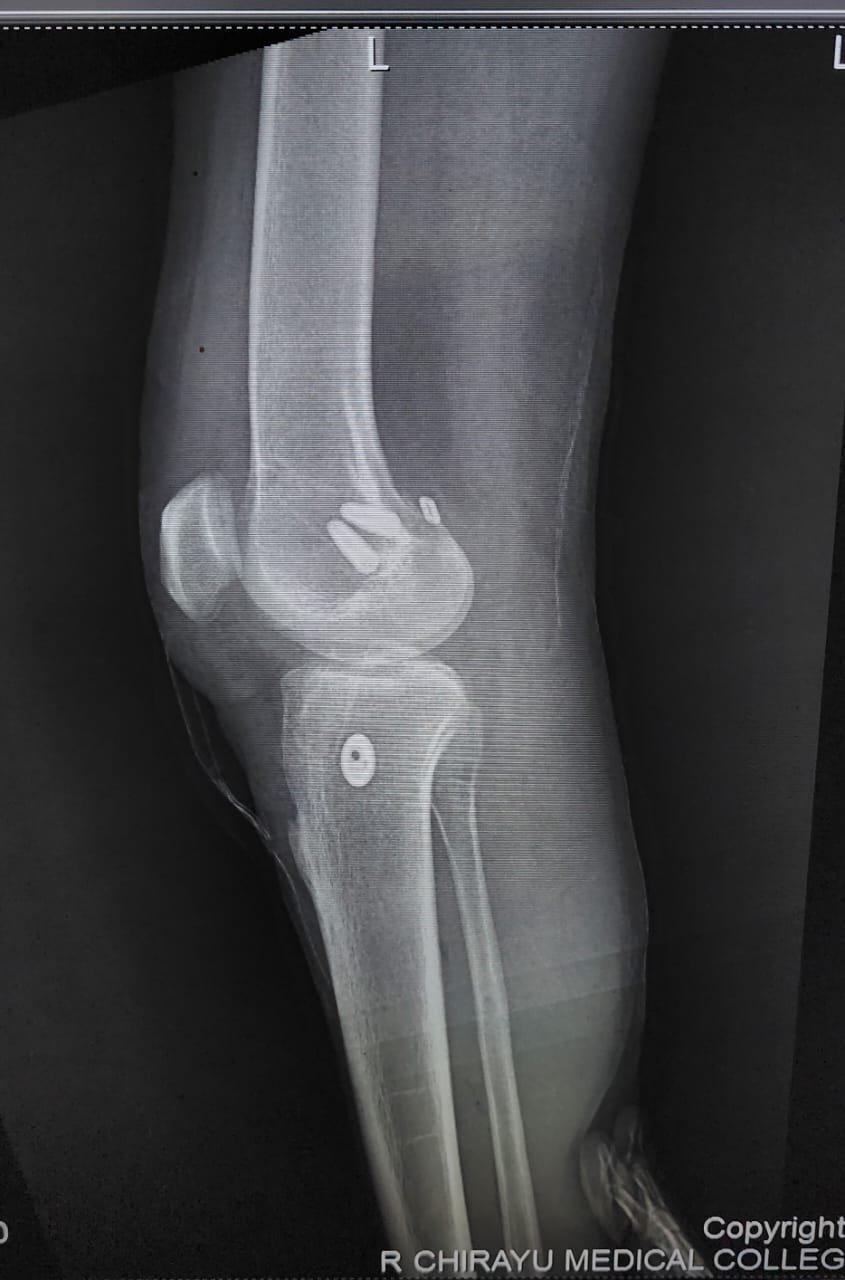

- ACL Reconstruction

- PCL Reconstruction

- Arthroscopy-Knee

- Fracture Treatment